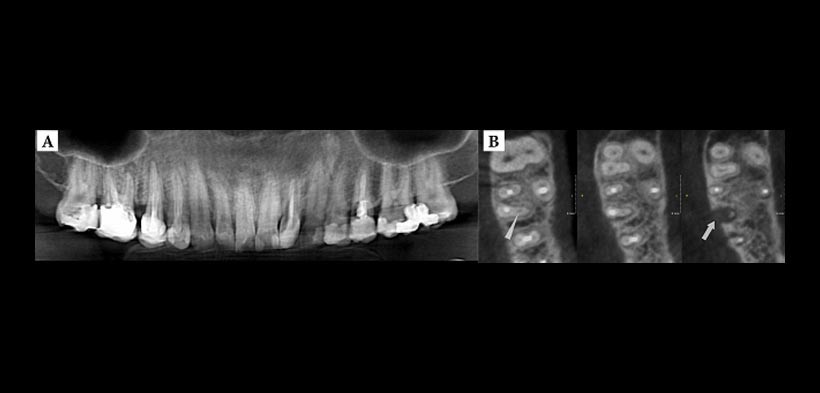

- DETALLES SOBRE LA MORFOLOGIA RADICULAR Y EL SISTEMA DE CONDUCTOS: Tridimensionalmente podemos encontrar conductos accesorios, bifurcaciones radiculares y la gran variedad y complejidad de todo el sistema de conducto. Todo esto es de importancia porque la falta de distinguir y tratar todos los canales pueden afectar negativamente a los resultados del tratamiento (fig. 1).

- DETECCION DE PERIODONTITIS APICAL: CBCT es significativamente más precisa y sensible que la radiografía convencional en la identificación de la periodontitis apical en los seres humanos (fig. 1, 3).

(Figura 1. A) Radiografía panorámica de un paciente que se queja de dolor dos años después del tratamiento de conductos en la primera molar superior derecho. B) La CBCT muestra a los cortes axiales el conducto mesiovestibular sin tratar (flecha) además de una lesión apical en la raíz mesiovestibular.